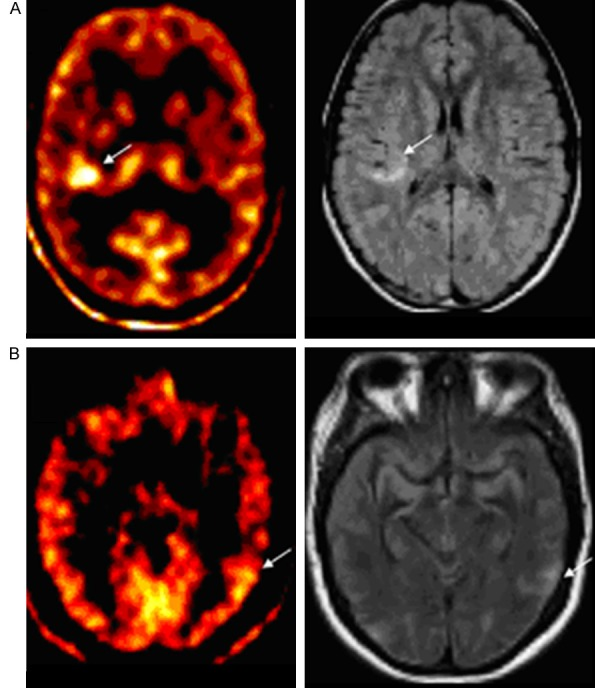

Рисунок 1. ФДГ-ПЭТ показывает обширный участок гипометаболизма в правой височной доле (стрелки) (А). ФМЗ-ПЭТ показывает точнее локализованный участок в мезиальной височной области у того же пациента (стрелка) (В). Симметричное распределение ФМЗ у здорового человека

Рисунок 4. C-WAY-100635 ПЭТ у пациента с МРТ-негативной височной эпилепсией. И ЭЭГ фокусом в правой височной доле. А. Т1 аксиальное МРТ не показывает структурных аномалий. В. C-WAY-100635 ПЭТ показывает ассиметричное снижение плотности и в латеральной и в мезиальной частях височной доли.